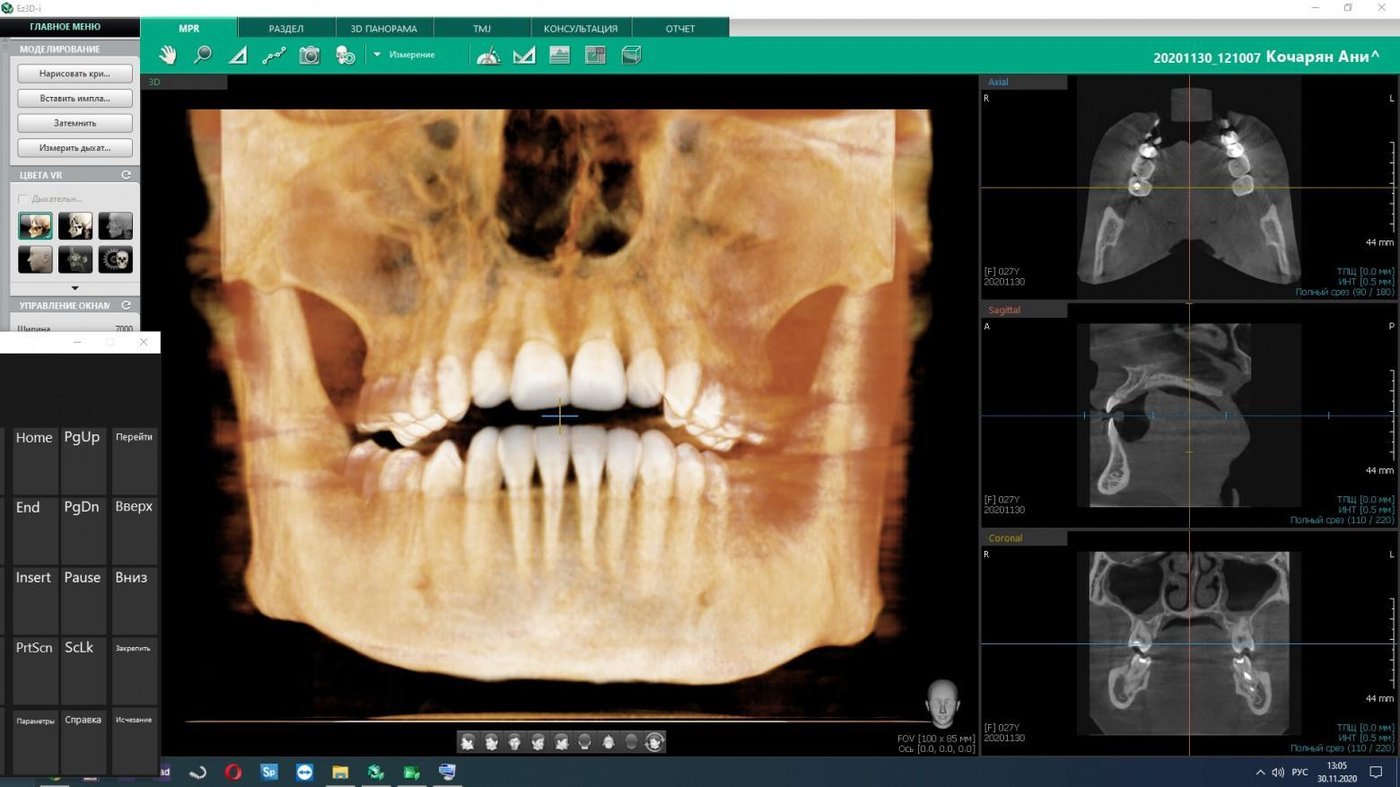

КТ высокого разрешения — понятно.

Важно делать быстро. Вот я прямо в кабинете получаю к ней доступ, пока пациент лежит:

К слову, у нас нет бумажных снимков, но есть негатоскопы (просмотровые столы). Потому что таковы требования нормативов.

Интерпроксимальные снимки, где на один снимок помещается сразу восемь контактных поверхностей, делают редко, а они важные, потому что видно кариес самый-самый маленький. КТ помогает увидеть все зубы в объёме, в повороте, видно все воспаления. Телерентгенограмму делают в основном ортодонты или при сложном ортопедическом лечении. Это специальное исследование для проведения антропометрических исследований, то есть оно даёт снимок головы один к одному, и можно проводить угловые измерения величины. Фотопротокол важен для сравнений до и после, потому что это важно и пациенту, и врачу для обучения. Если фотопротокола нет, то через несколько лет будет сложно восстановить картину.